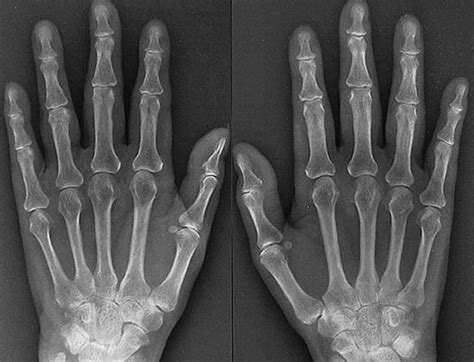

When you experience pain, swelling, or a limited range of motion in your fingers or wrist, your healthcare provider may recommend an X-ray of hand to get a clearer picture of what is happening beneath the skin. This common diagnostic tool is often the first line of defense in identifying bone-related issues, ranging from subtle hairline fractures to the degenerative effects of arthritis. By utilizing small doses of radiation, an X-ray creates detailed images of the intricate internal structures of the hand, providing essential information that is invisible during a standard physical examination.

The human hand is a complex structure comprised of 27 bones, along with numerous joints, tendons, and ligaments. Because of its constant use in daily activities, the hand is highly susceptible to injuries and chronic conditions. An X-ray of hand is requested by physicians to accurately diagnose a variety of clinical presentations. Without this imaging, it would be impossible to distinguish between a soft-tissue injury, such as a sprain, and a structural injury, like a fracture.

• Suspected Fractures: Detecting breaks in the phalanges (fingers), metacarpals (palm), or carpals (wrist).

• Arthritis Assessment: Identifying the loss of joint space, bone spurs, or cartilage erosion associated with osteoarthritis or rheumatoid arthritis.